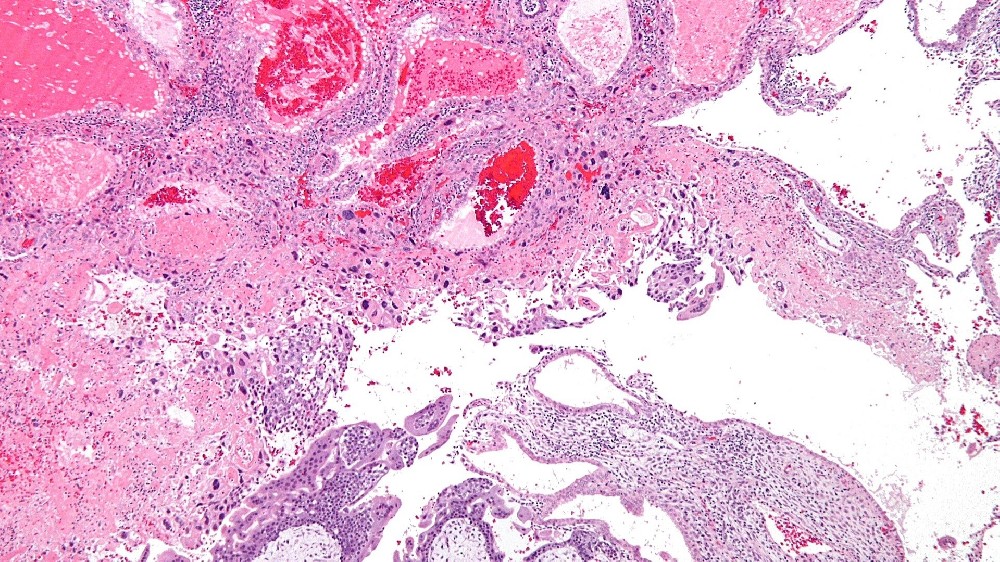

妊娠滋養細胞疾病 (Gestational Trophoblastic Disease, GTD) 是一種罕見的腫瘤,源自胎盤組織,特別是滋養細胞。滋養層細胞通常在懷孕期間發育成胎盤,幫助滋養胚胎。然而,滋養母細胞的異常可導致不受控制的生長,形成腫瘤或囊腫,並啟動妊娠滋養細胞疾病 (GTD)。

在全球範圍內,每 1,000 名孕婦中約有 1 例發生妊娠滋養細胞疾病 (GTD),其亞型各異,包括水滴形痣 (包括完全性和部分性)、浸润性痣、絨毛膜癌和胎盤部位滋養細胞瘤。然而,地區性的差異很普遍,特別是在香港和亞洲其他地區,GTD的發生率較高。

雖然與 GTD 有明顯關聯的特定遺傳基因非常罕見,但基因組研究突顯了與 GTD 亞型相關的染色體異常。例如,完全水滴形痣通常是由父系基因組重複所造成 (46XX 核型,完全源自父系)。相反地,部分水滴形痣通常會顯示三倍核型 (69 條染色體),混合母源與父源。

值得注意的是,GTD 細胞對葡萄糖攝取的異常依賴,代表了針對性治療的主要新陳代謝弱點。這些滋養細胞具有類似 Warburg 效應的特徵,會快速大量消耗葡萄糖,加速細胞生長並促進惡性發展。

妊娠滋養細胞疾病 (Gestational Trophoblastic Disease,GTD) 特別利用新陳代謝的弱點,如葡萄糖消耗增加 (Warburg 效應),加速快速生長和子宮擴張。持續嘔吐和荷爾蒙驅動症狀增加等症狀顯示腫瘤新陳代謝失控和 hCG 分泌過多。

由於胎兒細胞複製異常及胎盤形成受損,導致子宮擴大及葡萄狀泡形成。